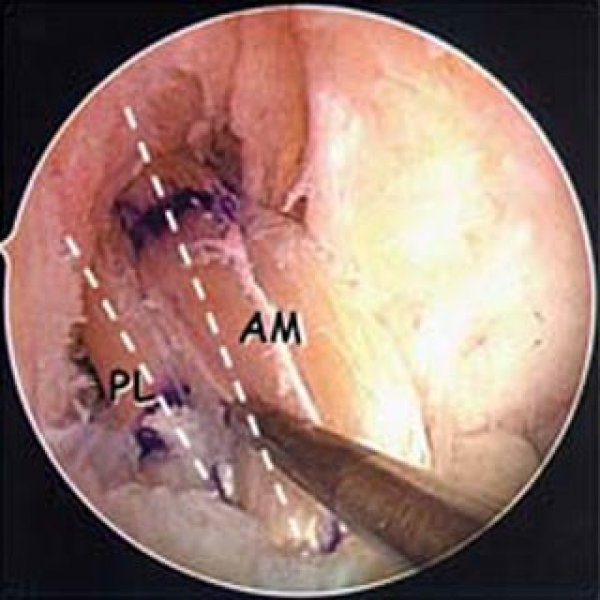

Προϊόντα / Υπηρεσίες Αρθροσκοπική Χειρουργική γόνατος, ώμου, ποδοκνήμης Αθλητικές Κακώσεις Αρθροπλαστική Ελαχίστης Επεμβατικότητας μικρών τομών Χειρουργική Σπονδυλικής Στήλης Ρομποτική Χειρουργική Παθήσεις του γόνατος Παθήσεις του ισχίου Παθήσεις του άκρου ποδός Παθήσεις του ώμου Παθήσεις του χεριού Παθήσεις της σπονδυλικής στήλης Κατάγματα